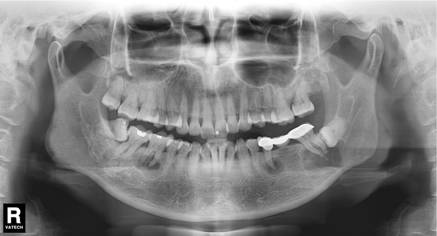

患者是30多岁的年轻男子,红色标记那颗牙松动,要求拔牙,开始嫌麻烦不愿拍片,后来经过再三劝说还是拍了片。结果把所有人包括他自己都吓了一跳。估计是良性,具体还得去医院住院手术做病理检查,所以大家不要忽视一张片子带来辅助检查的重要性。

试想,如果没有拍片,直接贸然拔牙,一旦出现问题......一张牙片,“救”了诊所,也救了患者!

通过x线片不仅能了解牙齿本身的病变情况,还可以了解牙根下有没有囊肿、周围骨头有没有吸收以及牙槽骨内是否有埋伏牙、多生牙等。依据X线片综合分析,可以提高齿科医生诊断治疗牙齿的准确性和成功率。

由于牙齿下部隐藏在牙槽骨中,口腔医生要了解牙齿的整体情况就需要拍摄全景片;要了解个别牙根及周围变化,则选择拍摄小牙片。